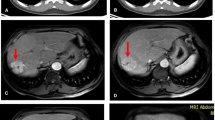

a–d Representative case of rim-shaped FDG uptake. A 63-year-old women who had hepatocellular carcinoma (HCC) in segment 8 received radiofrequency ablation (RFA) treatment. The fused PET/CT (a) and PET (b) images performed 1 day after RFA show rim-shaped increased FDG activity surrounding the ablation zone. The uniform peripheral enhancement is noted on contrast-enhanced arterial-phase CT 1 day after RFA (c). On follow-up, a CT image obtained 39 days after RFA (d) demonstrates loss of enhancement, which is indicative of benign periablational enhancement

Increased FDG accumulation in inflammatory and infectious processes is well recognized [22, 23]. Reactive tissue changes, such as focal hyperemia and inflammation, are depicted in the periphery of the ablated lesion soon after RFA, PEIT, and TACE, and show a uniform and peripheral FDG uptake [9, 24–26]. Therefore, the authors regarded a rim-shaped FDG uptake surrounding a target lesion after interventional therapy as negative, despite the greater activity than normal liver.

Visual analysis of the present study showed high sensitivity but moderate specificity. Kim et al. reported that sensitivity, specificity, PPV, NPV, and accuracy of FDG PET/CT for viable HCC during early post-embolic period were 100, 63, 84, 100, and 88 %, respectively [11]. In a study of FDG PET/CT after TACE combined with RFA for HCC, Zhao et al. demonstrated the high efficacy of early post-therapeutic PET/CT with 90.9 % positive detection rate [27]. These findings are similar to our results. In the pattern-based analysis, 8 of the 10 rim-shaped uptake lesions were determined as true negative. This result strongly demonstrated that not all hypermetabolic lesions could be considered residual tumor, even if they showed greater FDG activity than the surrounding liver. It will be necessary to consider FDG uptake pattern to provide more accurate treatment response. Furthermore, of the 27 lesions with eccentric, nodular, or scattered patterns, 21 lesions were diagnosed as true positive.